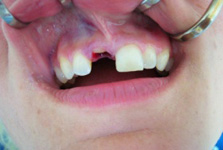

Náhrada jednoho zubu

Klasickým příkladem a indikací pro použití implantátu je ztráta jednoho zubu (v tomto případě v předním – frontálním úseku) v jinak zdravém, nepoškozeném chrupu.

Nejčastější příčinou takové ztráty je sportovní nebo dopravní úraz.

Náhrada jednoho zubu pomocí implantátu je možná také v postranním úseku chrupu. Při ztrátě většího počtu zubů ve frontálním nebo postranním úseku může být mezer uzavřena větším počtem jednotlivých implantátů.

Při ošetření pomocí jednotlivých implantátů zůstávají sousední zuby neporušené – intaktní. Při klasickém ošetření pomocí můstků musejí být tyto zuby obroušeny!